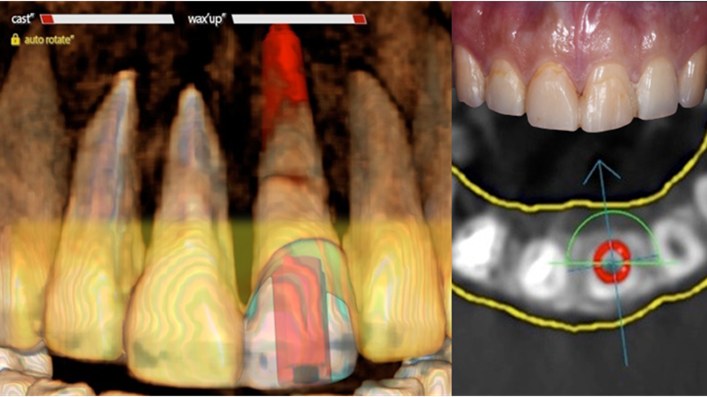

Clinical case: Extraction, immediate placement & loading using

R2GATE solution in aesthetic zone

- Courtesy of Dr. Jong-Cheol Kim, Korea-

Dr. Jong Cheol Kim, immediate loading, digital guided surgery, Digital ONE-DAY Implant, maxillary anterior, #21, guided surgery, immediate loading, AnyRidge, R2GATE, Mega ISQ, MEG Torq, R2GATE Full Surgical Kit

AnyRidge implant system, R2 Guide, R2GATE Full Surgical Kit, Mega ISQ